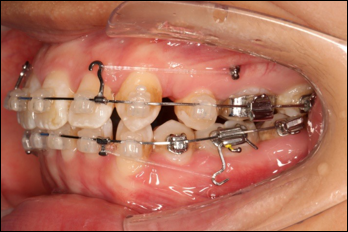

拔除14、24、34、44,上颌TPA+上颌高位支抗钉

2.第2.5个月:2017.1.13 ◆ 上颌加TPA,植入1312-08种植钉,上下0.16cu-niti

3.第3.5个月:2017.02.16 ◆ 上下0.014*25 cu-niti,50g 尖牙远中

4.第6个月:2017.04.28 ◆ 上0.016*25ss 13/23v形曲,下0.017*25ss

5.第7个月:2017.05.26 ◆ 下颌36/46加power arm

6.第9个月:2017.07.25 ◆ 上前牙加颈部弹力线

7.第13.5个月:2017.12.15 ◆ 36/46远中倾斜,改变下颌牵引位置

8.第17个月:2018.03.01 ◆ 上tpa加17/27牵引钩,压低;下颌43/32重粘,下颌0.016*25niti

9.第20个月:2018.5.25 ◆ 拆tpa,16/26粘tube上和0.14*25cu-niti 下颌0.018*25niti

10.第22个月:2018.7.23 ◆ 上颌 0.010*25TMA,下颌0.017*25ss43压低曲,双侧后牙垂直牵引

11.第23个月:2018.09.29 ◆ 15/43/16/7/11/21重粘,上0.016*25cu-niti 下0.018niti 上连扎

12.第24.5个月:拆除矫治器,粘接上下舌侧保持器

2016.10.31  初戴,0.013cu-niti2017.1.13  上颌加TPA,U56间斜形植入韩国庆北1312-08种植钉,上下0.16cu-niti

2017.02.16  上下0.014*25 cu-niti,50g 拉尖牙远中

2017.04.28  上0.016*25ss 13、23近远中约5度 v形曲,下0.017*25ss

2017.05.26  磨牙近中倾斜,下颌36、46加power arm

2017.07.25  上前牙加颈部弹力线

2017.10.07  继续关间隙,下颌使用水平关间隙

下颌磨牙通过powerarm直立效果明显,下颌整平效果明显

2017.12.15  继续关间隙

2018.03.01上TPA加17、27颚侧牵引钩,压低17、27颚尖下颌43、32重粘,下颌0.016*25niti

2018.04.20  间隙基本关闭,上颌重新整平,精调

2018.5.25  (19个月)拆TPA,16、26粘tube 上颌0.14*25cu-niti  下颌0.018*25niti2018.7.23  上颌 0.017*25TMA,下颌0.017*25ss43压低曲,双侧后牙垂直牵引

2018.09.29  15、43、16、17、11、21重粘,上0.016*25cu-niti 下0.018niti 上连扎